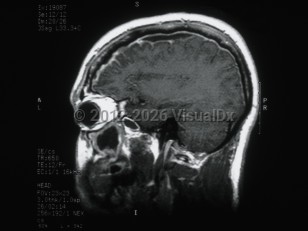

Idiopathic intracranial hypertensionIdiopathic intracranial hypertension

PapilledemaPapilledema

MeningiomaMeningioma

CraniopharyngiomaCraniopharyngioma